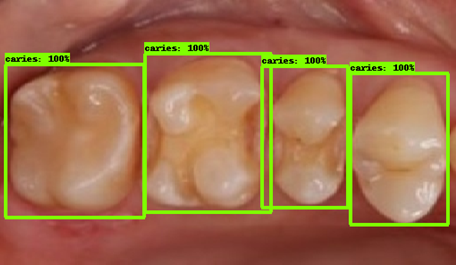

| 모델예측 | 정답 |

|---|---|

![]() |

- 인식이 잘 되지 않은 케이스들을 보면, 사람의 눈으로 뚜렷하게 충치로 판단되는 치아를 모델이 잡아내지 못하는 경우도 있었지만, 그보다는 사람의 눈으로도 충치로 분류하기 어려운 경우에 모델역시 잘 분류해내지 못하는 것을 볼 수 있었습니다. 예를 들어, 인식이 잘되지 않은 첫번째 케이스, 세번째 케이스를 보면 정답지에는 충치 치아로 분류되어 있지만, 사람이 한눈에 보기에도 충치라고 판단하기 어려운 사진들이었습니다. 이러한 경우에 모델은 잘 잡아내지 못하고 있습니다.